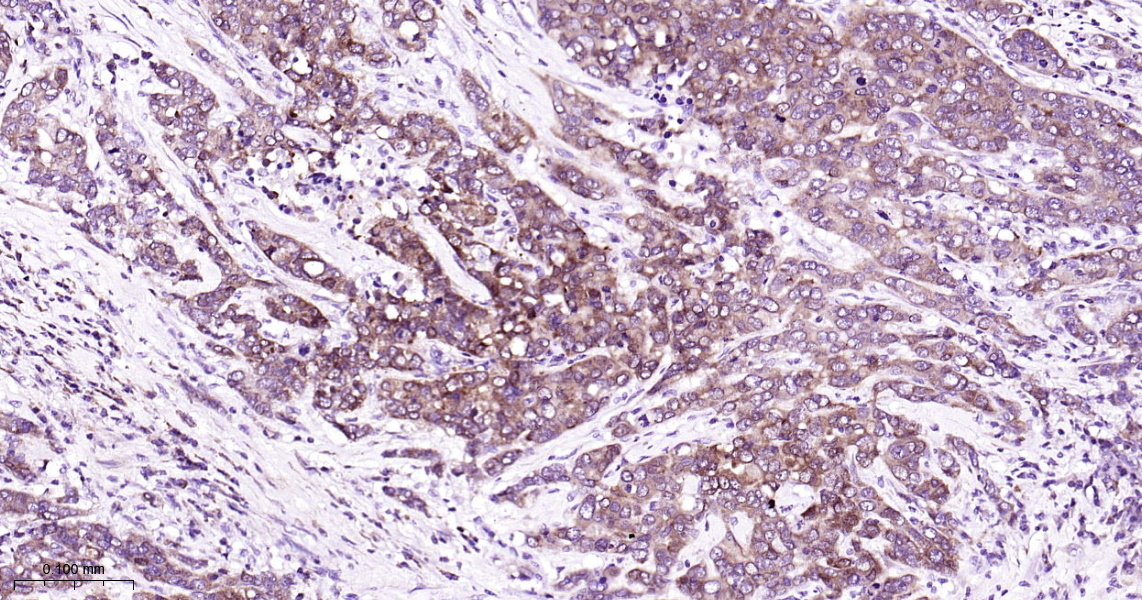

• IHC-P

Applications WB, IHC-P, IHC-F, IP, IF, ICC/IF

IHC-P 1:200-400